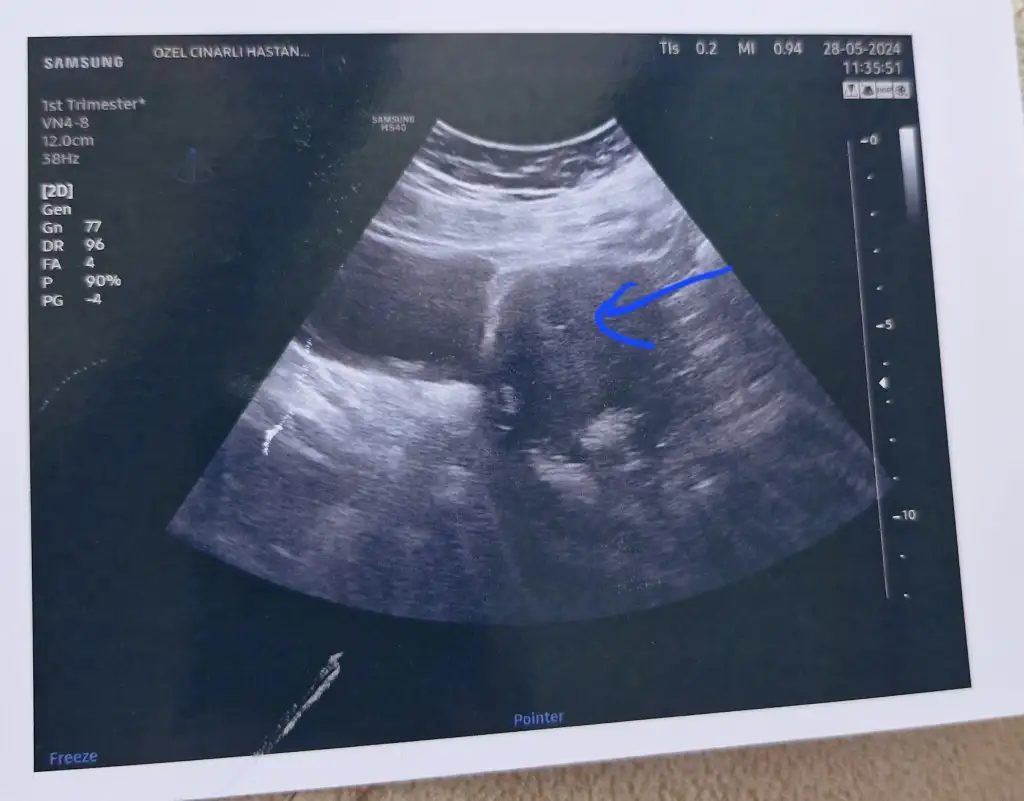

Sonucu attım burada çok net çıkmamış ama ekranda netti. Yolk ve sac hakkıda birşey demedi herşey çok iyigidiyor dedi estrofemi kesti progestan folikasit ve voraspirine devam.olumsuz birşey demedi. Sizce yolk ve saç var mı. Bebek henüz gözükmüyor dedi